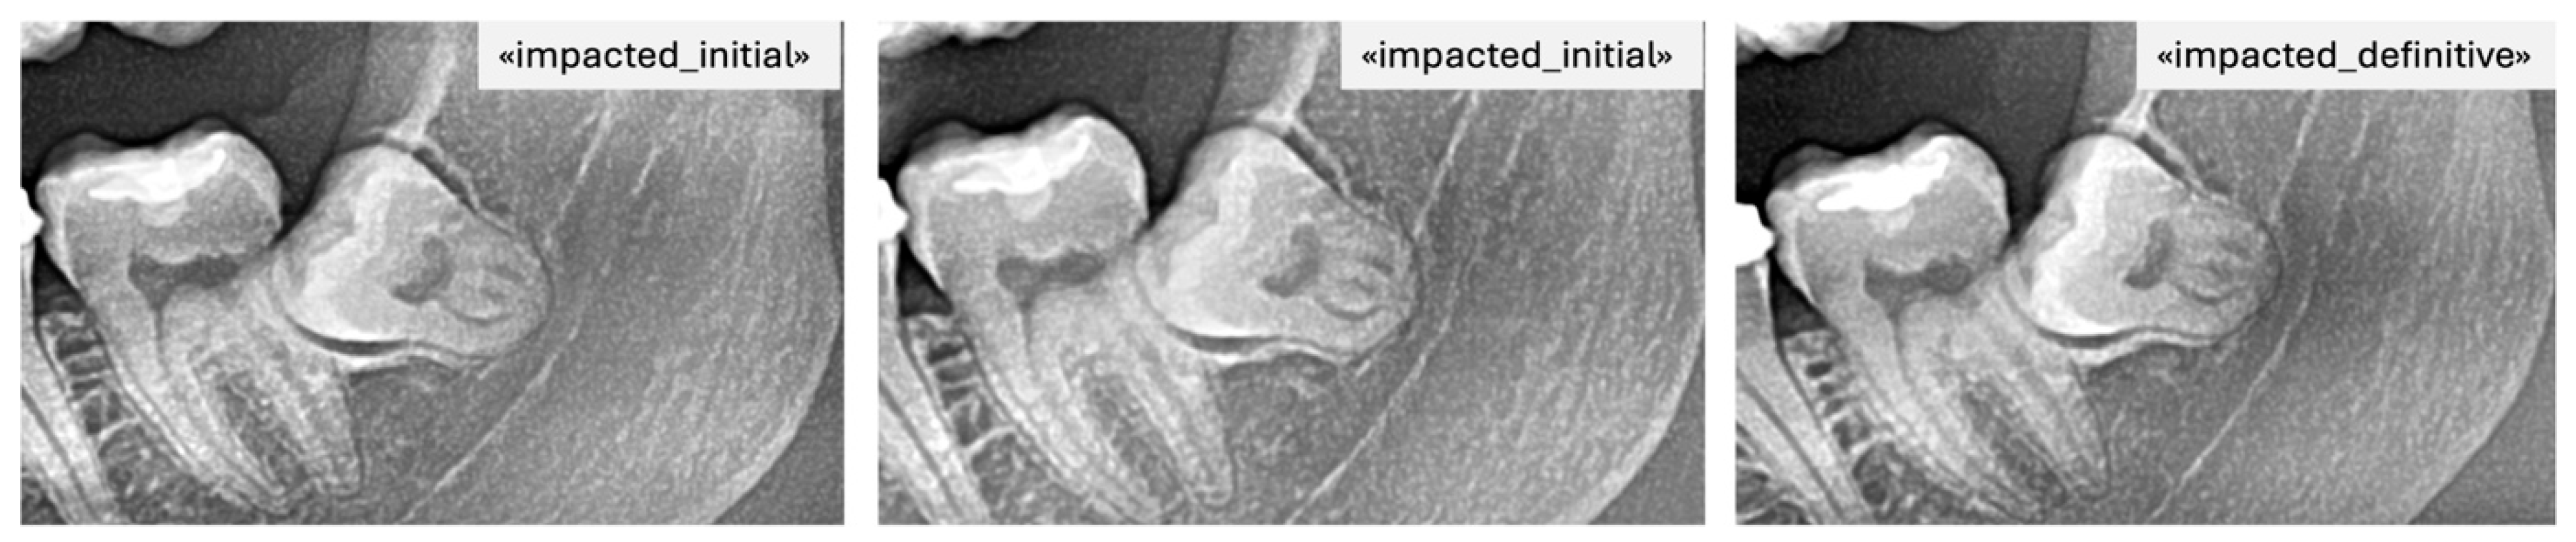

- Partially impacted: the occlusal surface was below the occlusal plane but partially exposed, with part of the crown still covered by alveolar bone or showing limited eruption space between the distal of the second molar and the anterior border of the ramus.

- Impacted: the third molar was entirely below the occlusal plane, with full bone coverage and/or evident spatial limitation or unfavorable angulation (e.g., mesioangular or horizontal position) in relation to the second molar.